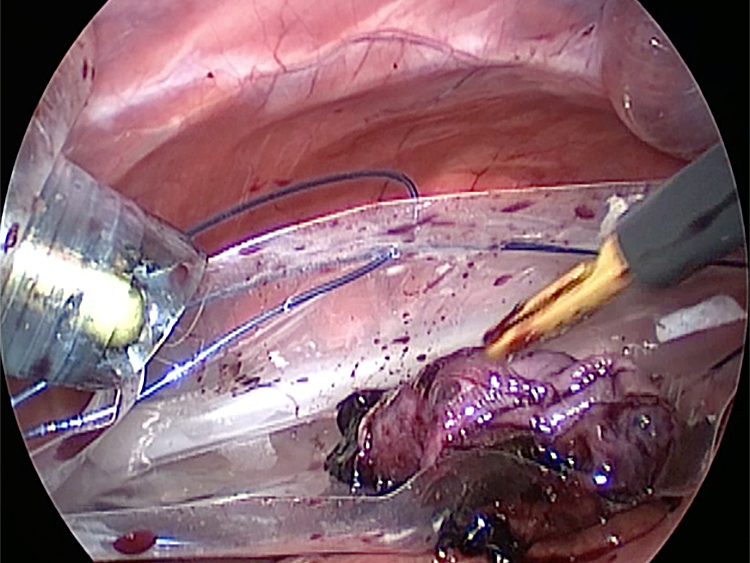

体の外に出すためお腹の中で袋に入れていきます。

このときに胆嚢と一緒にクリップやガーゼも回収します。そしてお腹の中をきれいにしていきます。

回収袋にいれて体外に摘出していきます。

摘出した胆嚢はカチカチで中にはゼリー状の硬い物質が詰まっていました。